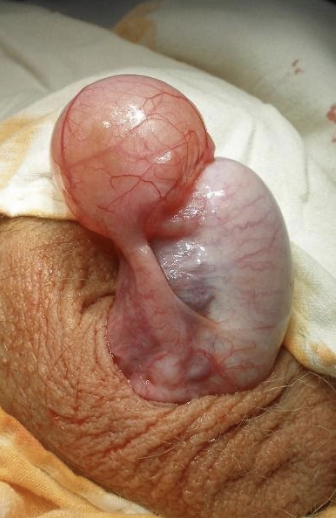

- #Поєднана водянка оболонок яєчка та сім’яного канатика , - #hydro-funikulocele.

- #Багатокамерна водянка, поєднана водянка оболонок яєчка та сім’яного канатика.

Як показано на схемі сполучення з черевною порожниною немає. У вагінальному відростку очеревини залишилась рідина з черевної порожнини, - утворюється водянка оболонок яєчка – hydrocele. Також може бути рясна секреція рідини серозними листками оболонок яєчка, - утворюється напружена водянка оболонок яєчка, або напружена загальна водянка оболонок яєчка та сім’яного канатика.

Якщо водянка сполучається з черевною порожниною вузьким ходом то через нього не може проникнути кишка чи інший орган черевної порожнини, а проникає серозна рідина. В цьому випадку водянка називається сполучена водянка оболонок яєчка чи канатика, - hydrocele communicans, funiculocele communicans. Вони можуть симулювати грижу.